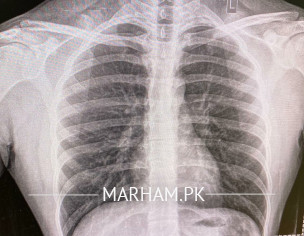

Asking For Other, Male 27, Rawalpindi

concerned person has low grade fever and dry cough for 2days. blood CBC is normal except slightly raised lymphocytes .

X ray seems to be normal. in corona usually WBCs are low. start anti biotic and panadol after proper consultation